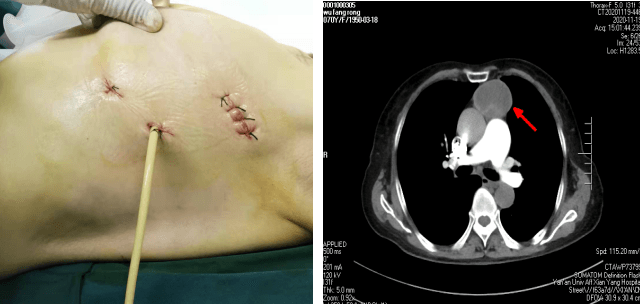

患者××,女,70岁,因“间断腹部不适2月,加重10天” 于11月23日收入肿瘤/胸外科。胸部CT示前纵膈肿瘤。苗满园主任带领团队对该患者情况进行了仔细的研究讨论:纵膈肿瘤大小约10cm×6cm×6cm,边界尚清,内有钙化,考虑良性肿瘤可能性大。与家属沟通后选择胸腔镜下手术。手术团队经精心术前准备,于11月25日为患者实施全麻下“胸腔镜下纵膈肿瘤切除术”。术中发现肿瘤起于心脏左前上方,经主动脉弓前达胸腔顶。术中仔细分离,克服因心脏跳动及主动脉搏动的不稳定性,保护好心脏、膈神经、主动脉,出血量少,手术十分顺利,历时1小时,完整切除肿瘤。严格按围手术期ERAS管道管理改进措施,选用留置导尿管单根引流,避免传统手术因引流管粗硬导致的术后疼痛不适,术后当天即可独立下床活动,生活完全自理。患者及家属非常满意,极大地提高了患者的就医体验。